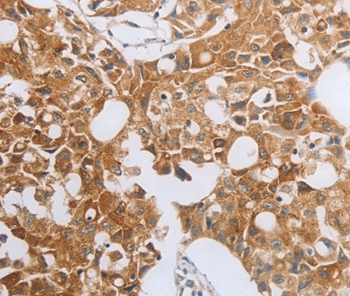

Immunohistochemical analysis of paraffin-embedded Human lung cancer tissue using #35824 at dilution 1/40.

Immunohistochemistry: 1:25-1:100